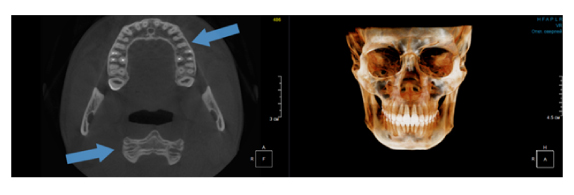

Когда мы отправляем пациента на проведение рентгенологического исследования, то подвергаем его определенному риску. Именно это нужно осознавать, так как в радиологии нет минимально безопасной дозы, поэтому любое назначение должно быть обоснованным. В связи с этим поле обзора является достаточно принципиальным параметром. Если вы врач-терапевт, занимающийся эндодонтией или ортопед, который решил оценить состояние зубов перед протезированием, то вы должны понимать, что проведение исследования с полем обзора 10x10 см будет гораздо информативнее нежели большие снимки (18x16 см и выше). В первую очередь это связано с размером вокселя, о нём я напишу чуть ниже, а второе это то, что вам придется увеличивать изображение по каждому корневому каналу, и от этого вы будете терять в качестве снимка (рис. 1). И ситуация наоборот, если вы ортодонт, то чтобы использовать весь диагностический потенциал, а также возможность загрузить данные для расчёта 3D цефалометрии, то вам нужны снимки, захватывающие весь лицевой отдел черепа. Таким образом, дентальный томограф должен обладать возможностью проведения исследований с разным FOV, обеспечивая нужды всех специалистов. Если ваша клиника базируется на терапевтическом, хирургическом и ортопедическом приёме, то на мой взгляд, можно рассмотреть дентальные томографы с полем обзора 10x10 см или 16x10 см. Последний больше актуален для тех, кто работает с ВНЧС, так как антропометрически в 16 см даже у брахицефалов сустав должен попадать. Если в клинике есть ортодонтическое направление, функциональная стоматология, ЛОР-практика или ЧЛХ, то, безусловно, вышепредставленные снимки не будут отражать всех данных, которые необходимы для диагностики и планирования лечения. Здесь лучше рассмотреть конусно-лучевые компьютерные томографы с зоной сканирования 18x16 или 20x20 см. Особо стоит отметить понятие «сшивки». Есть дентальные томографы, которые делают один цельный снимок размерами, которые описаны выше, а есть аппараты, которым нужно провести две экспозиции и сшить изображения вместе, чтобы получился необходимый объём исследования. Как правило, вторые томографы чуть дешевле, но всё зависит от того, насколько вам нужна максимальная точность исследования. Если при сшивке челюсти и зубы, как правило, совмещаются практически идеально, то на уровне позвоночного столба происходит наслоение тканей и от него уже не избавиться (рис. 2). Второй отрицательный момент – это износ оборудования, логично, что он будет быстрее, так что экономия средств — это ещё спорный вопрос.

Рис. 2. Левый снимок представлен исследованием 20x20 см единым изображением. Стрелками показаны чёткость канально-корневой системы зуба, а также позвоночника. Правый снимок представлен исследованием 16x15 см с функцией сшивки. Стрелками обозначены чёткость зуба, но двойной контур позвоночника.